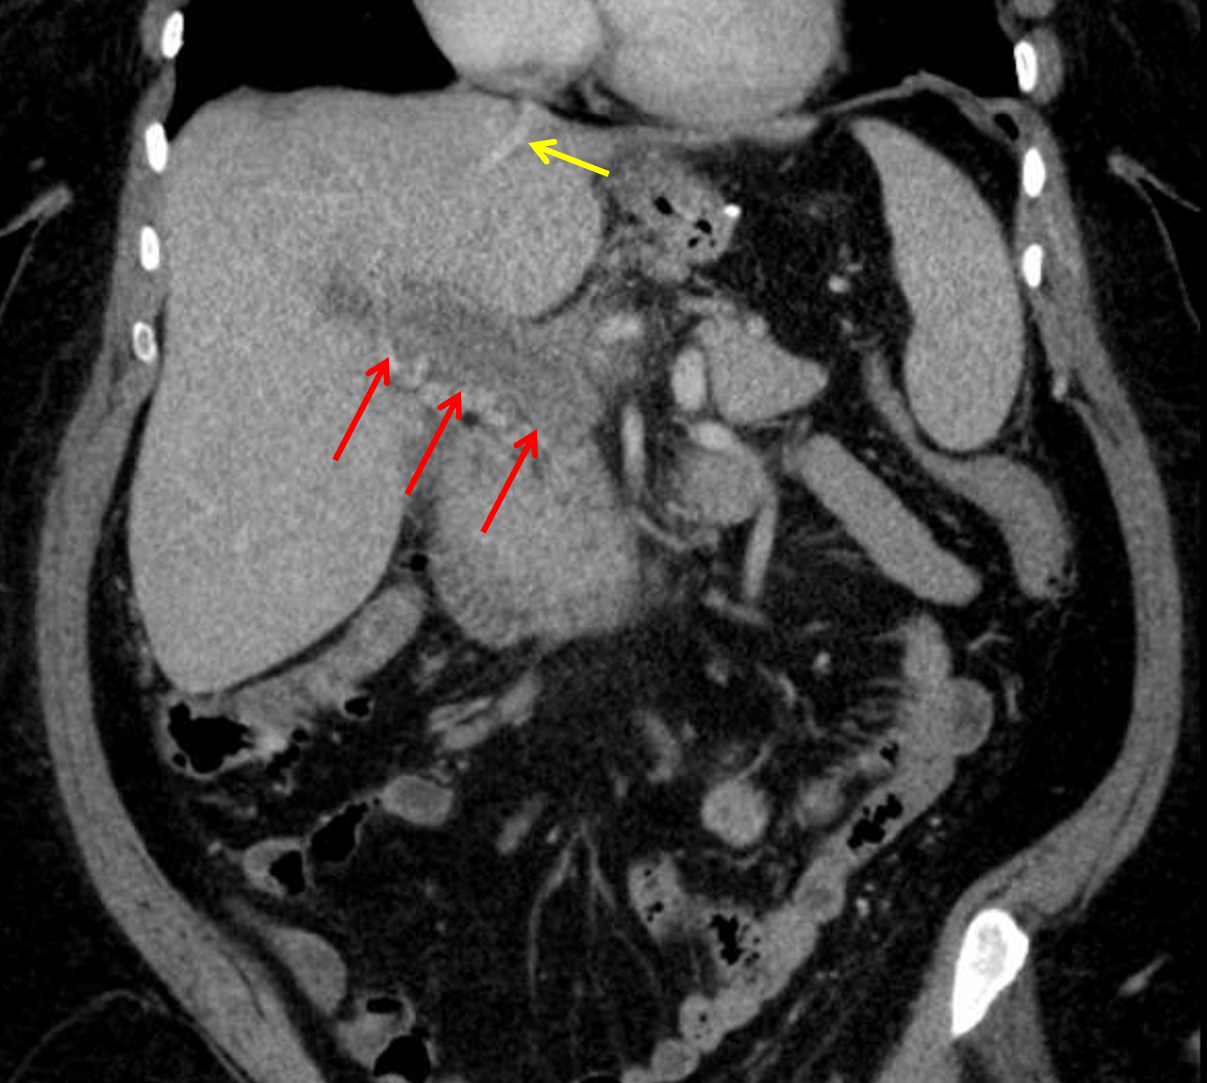

Age: 54

Sex: Female

Indication: Nausea, vomiting

Sample ReportExtensive portal vein thrombosis with extension into the splenic and right and left portal intrahepatic branches. Small geographic area of hypoattenuation adjacent to the falciform ligament may relate to altered perfusion.

Surgical changes of sleeve gastrectomy without bowel obstruction, loculated intraabdominal collection, or pneumoperitoneum.

Heterogeneous solid lesion in the interpolar left kidney. Recommend nonemergent renal protocol CT or MRI for further evaluation.